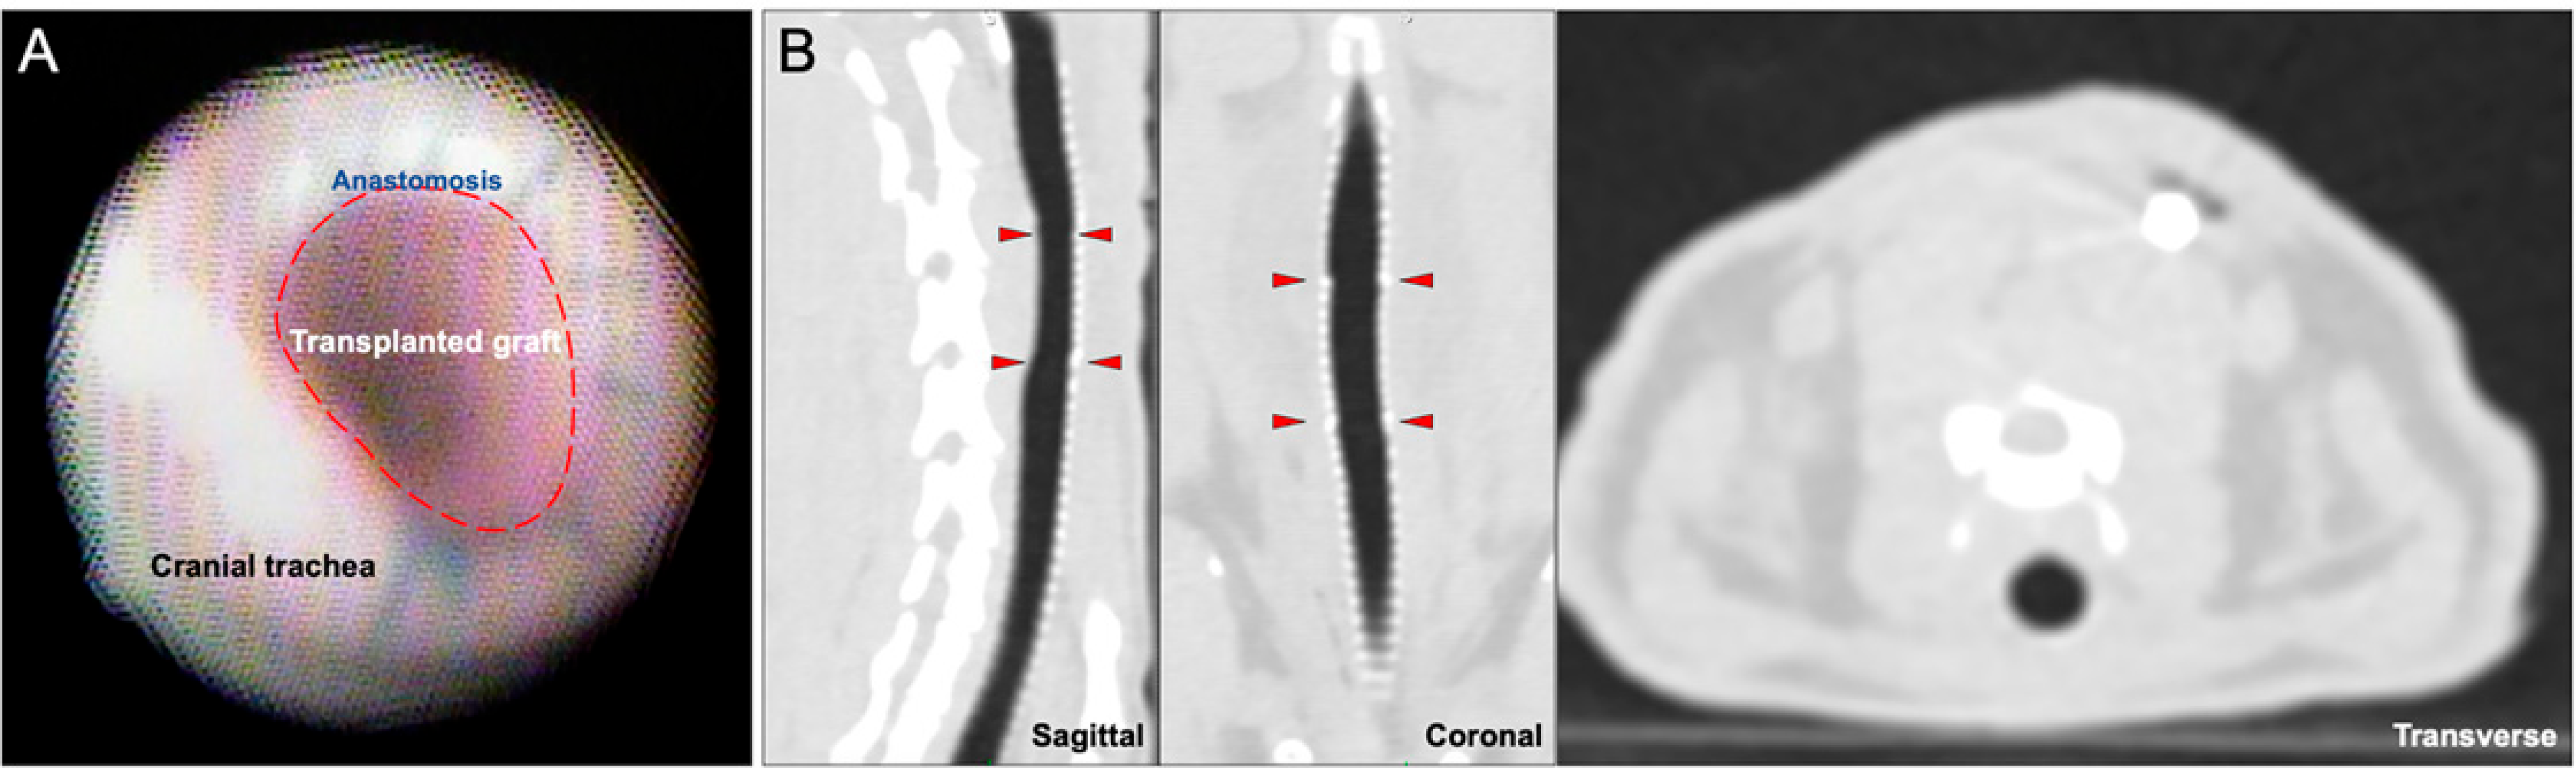

Bronchoscopic examination in all tracheas showed normal, pink mucosa without patches of ischemia or necrosis. There was scattered hyperemia that was not attributable to any one treatment group. No suture line dehiscence was observed, and the pediatric bronchoscope was able to traverse both the proximal and distal anastomoses without difficulty (Figure 2A). CT showed overall luminal patency without extra-tracheal air (Figure 2B).

Figure 2. Bronchoscopic and Radiographic Surveillance at 7 Days Post-transplant. (A) Bronchoscopy shows a patent tracheal graft without evidence of necrosis. (B) Sagittal, coronal, and transverse views show intact tracheal anastomosis without stenosis or extraluminal air suggestive of dehiscence. The red arrowheads indicate the proximal and distal anastomotic boundaries.